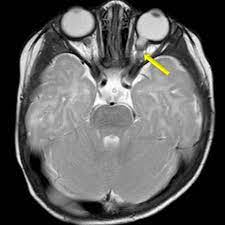

Humming Bird Sign Mickey Mouse Sign And Morning Glory Sign In Progressive Supranuclear Palsy Jalal Ma Menon Mk Menoufia Med J

Ultimate Radiology Hummingbird And Morning Glory Of Radiology